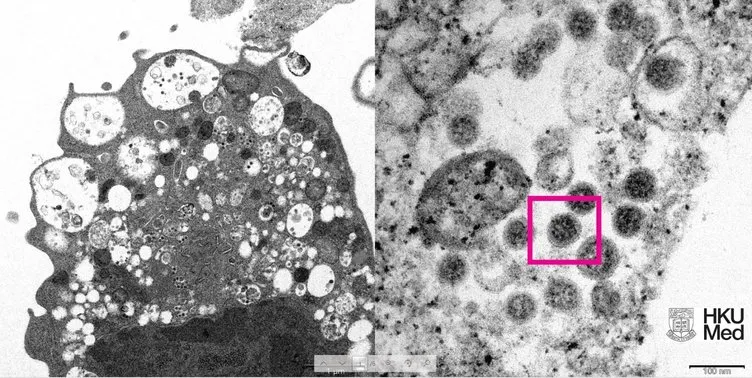

HKUMed'den yapılan açıklamada, araştırmacılar tarafından SARS-CoV-2 virüsünün Omicron varyantının elektron mikroskobu görüntüsünün ortaya çıkarıldığı belirtildi. Üniversite tarafından yayınlanan fotoğrafın solunda, küçük siyah viral partiküller içeren şişmiş veziküllerle hücre hasarını gösteren, SARS-CoV-2 Omicron varyantı ile enfeksiyondan sonra bir maymun böbrek hücresinin (Vero E6) düşük büyütmeli elektron mikrografının yer aldığı ifade edildi. Fotoğrafın sağında ise yüzeylerinde korona şekilli sivri uçlara sahip viral partikül kümelerini gösteren enfekte bir Vero E6 hücresinin yüksek büyütmeli elektron mikrografının yer aldığı belirtildi.